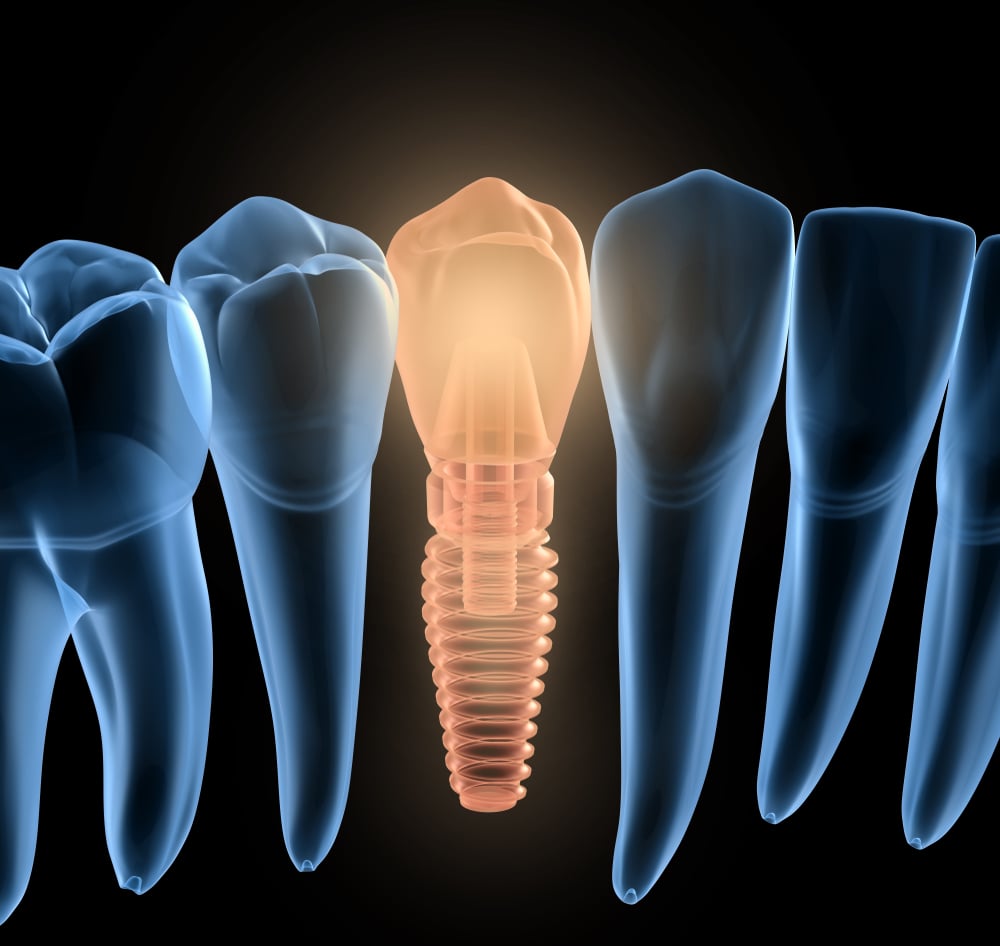

It’s not anything near the long, uncomfortable procedure many people may imagine they’ll need to undergo in order to get dental implants. Thanks to innovations

Dental implants are becoming an increasingly popular option for people who have one or more missing teeth. However, some patients are still a bit apprehensive

There are many health benefits to dental implants such as how they keep jaw bone density resilient and prevent surrounding teeth from shifting. However, many patients

Many patients are unaware of what makes a periodontist different than a general dentist, especially when it comes to the placement of dental implants. A

You want to restore your smile but you know it could take weeks or even months to complete the process with traditional dental implants. This

Did you know that approximately 120 million Americans are currently missing at least one tooth, according to data released by the American College of Prosthodontists?